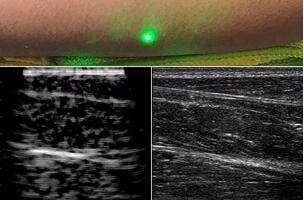

臨床應(yīng)用的無創(chuàng)超聲,要求探頭與人體皮膚直接接觸來向身體傳導(dǎo)高頻振動的超聲波。但是,有一些特定的患者卻在超聲檢查時受到限制,比如兒童、燒傷患者和敏感皮膚患者等。而近日麻省理工學(xué)院的研究人員證明,確實(shí)有可能使用激光在不接觸皮膚的前提下對患者進(jìn)行超聲波掃描。

而麻省理工學(xué)院的研究小組現(xiàn)在開發(fā)了一種使用激光檢測皮膚上超聲波振動的方法,以便可以使用一種激光使皮膚產(chǎn)生共振,而另一種則可以檢測到振動,從而達(dá)到“遠(yuǎn)程超聲掃描”的作用。

目前,研究人員已經(jīng)與健康的志愿者測試了他們的系統(tǒng):從半米遠(yuǎn)處掃描了他們的前臂,并將這些結(jié)果與傳統(tǒng)超聲的結(jié)果進(jìn)行了比較。他們能夠觀察到深達(dá)6厘米的組織,并能看到肌肉,脂肪和骨頭,并報(bào)告其結(jié)果可與標(biāo)準(zhǔn)超聲相媲美。

研究人員用一種激光裝置測試了這個想法,該裝置使用一個波長為1,550納米的脈沖激光來產(chǎn)生聲波,并使用第二個連續(xù)激光,調(diào)諧到相同的波長以遠(yuǎn)程檢測反射的聲波。第二個激光器是靈敏的運(yùn)動檢測器,可測量聲波從肌肉,脂肪和其他組織反射回來而引起的皮膚表面振動。反射的聲波產(chǎn)生的皮膚表面運(yùn)動會導(dǎo)致激光頻率發(fā)生變化,這種變化可以測量。通過機(jī)械掃描人體上的激光,科學(xué)家可以獲取不同位置的數(shù)據(jù)并生成該區(qū)域的圖像。